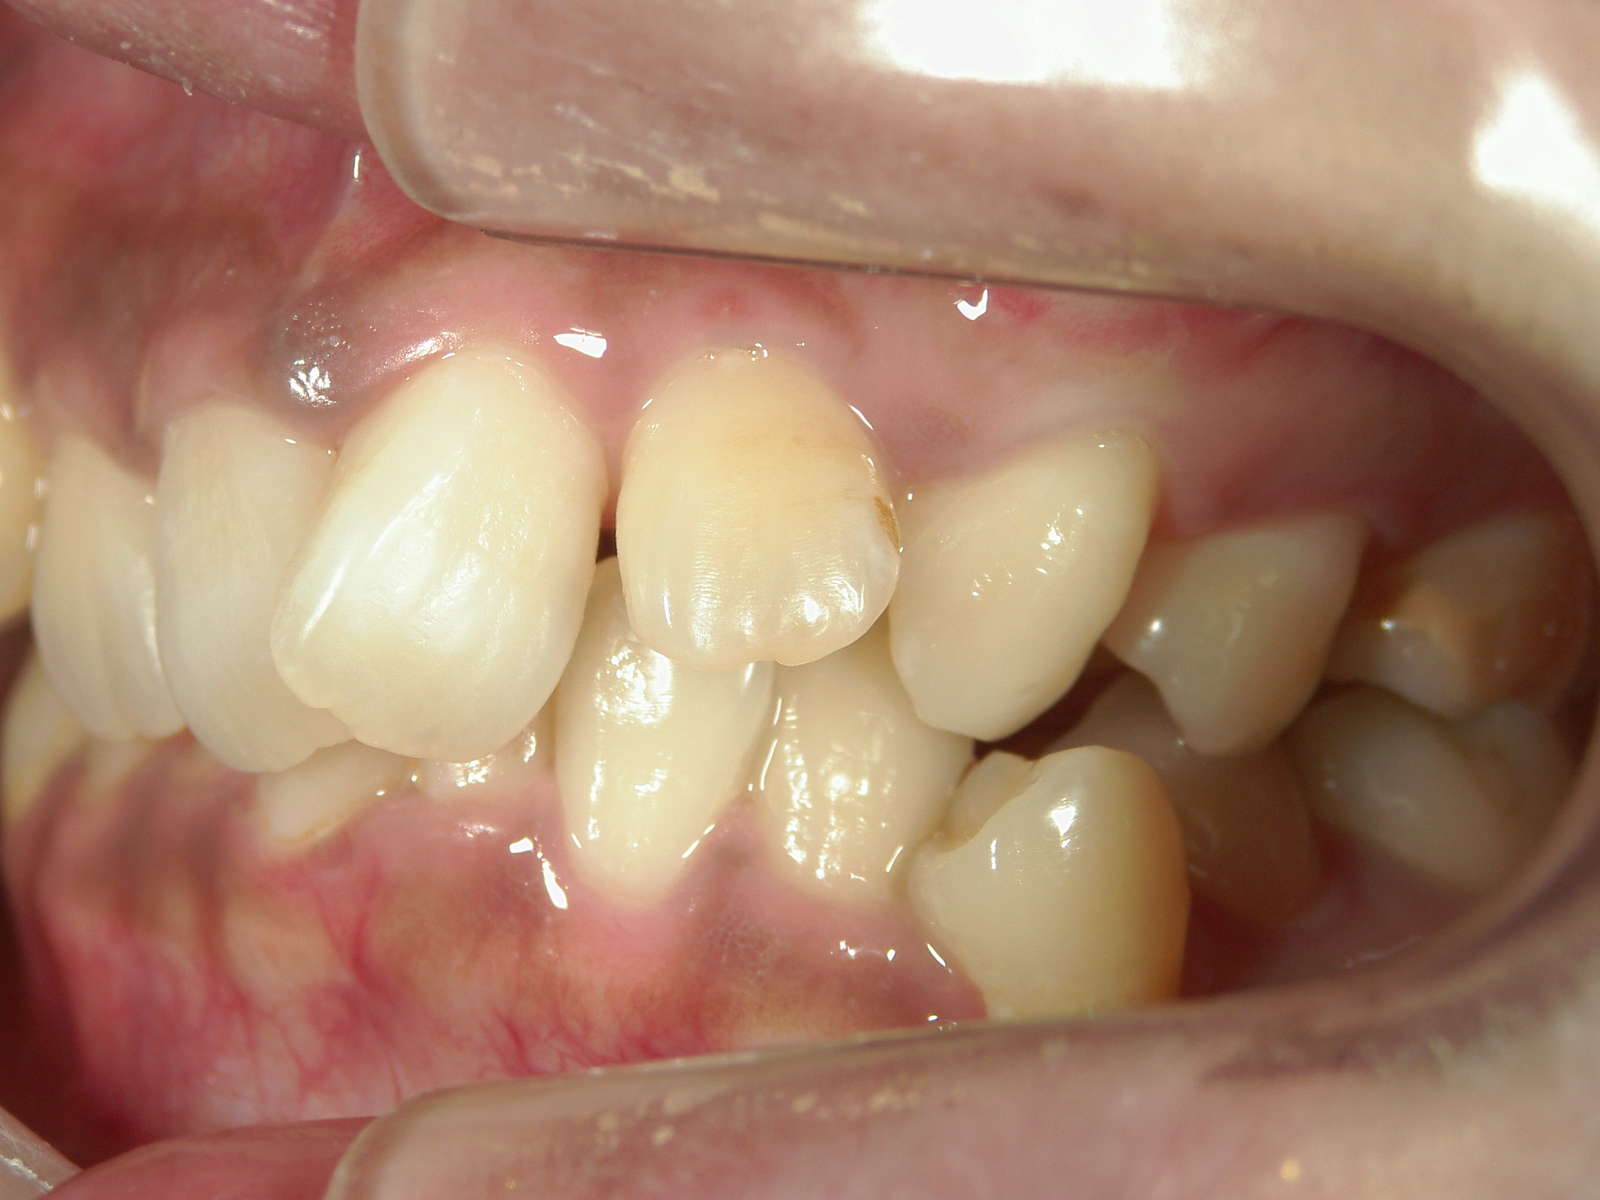

全顎ワイヤー矯正 症例(6)

Ⅱ級ゴム・ミニインプラントを併用

①叢生を改善しました。

カテゴリー : ガタガタ(叢生) , 噛み合わせが深い(過蓋咬合)